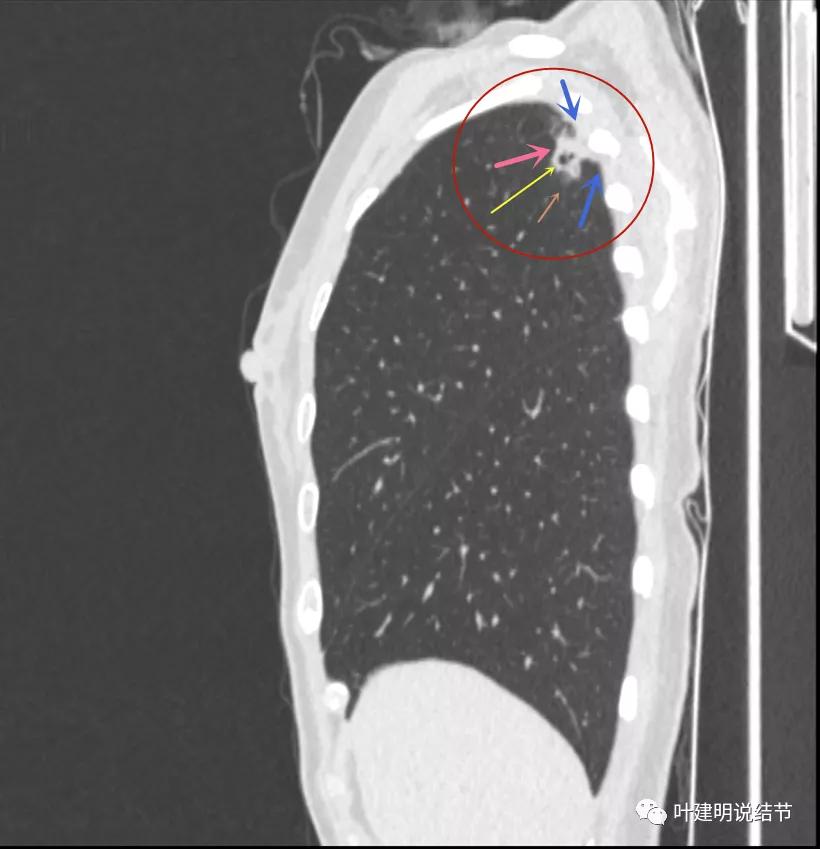

邻近胸膜增厚明显(蓝色箭头),病灶边上部分有淡磨玻璃(砖色箭头)

病灶与胸壁间不似毛刺,像炎性粘连(相连的结构粗细均匀,没有离开病灶后变细,密度较高,邻近胸膜也增厚的);有卫星状(绿色箭头);有淡且散的边缘不清的磨玻璃成分(砖色箭头)

病灶密度高,膨胀性弱,有中间空洞(黄色箭头),囊壁密度过高(粉色箭头);有淡磨玻璃成分(砖色箭头)以及邻近胸膜的明显增厚(蓝色箭头)